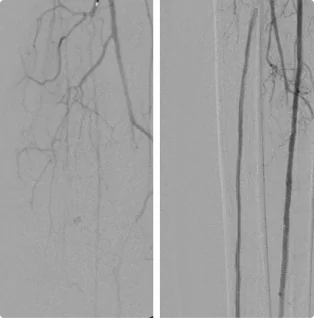

Female – Age 78

Referred by her Podiatrist for Severe Calf Pain, Non-Healing Wounds and Absent Toe Pulses

This patient had already been told by a different vascular specialist that there was nothing that they could do for her severe pain. The blockages in the arteries in her legs were so severe, no pulse could be felt in her toes. After ultrasound and evaluation, Dr. Goldstein concluded intervention was possible. Using advanced interventional techniques, He successfully cleared her arteries in both legs. Her pain subsided and her wounds healed over time. The team at Pedes Orange County regularly monitors her arterial flow to ensure she remains pain and ulcer-free.

Before

Arterial flow through the right knee and into the calf before intervention. The blockages below the knee are so severe that no clear flow exists down into the toes, causing severe pain as the muscles and tissue starve of blood.

After

After working to clear the blockages from both sides, Dr. Goldstein establishes flow through the two lower branches of the arteries, allowing blood to flow down into the foot.